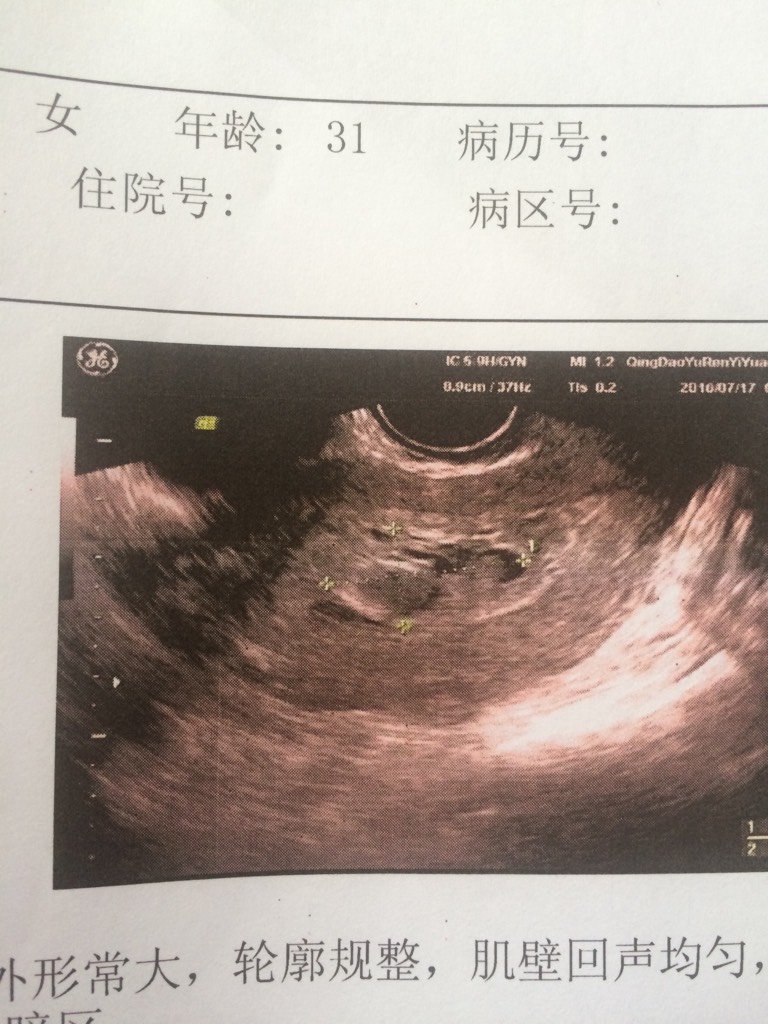

大家帮忙看看快愁死了,怀孕两月做B超啥也看不见,阴超医生说像葡萄胎,没啥反应不出血,谢谢大家 大家帮忙看看快愁死了,怀孕两月做B超啥也看不见,阴超医生说像葡萄胎,没啥反应不出血,谢谢大家 点击展开 151*****183_a9PJ 2016-07-18 15:36 为您推荐: 其他回答 很有可能, 思思~, 2016-07-18 16:33 是的 С¿ѧ 2016-07-18 15:58 建议不用再吃保胎药了。没有心肯定是不正常。 С¿ѧ 2016-07-18 15:55 祝宝妈好孕 小妍米爱 2016-07-18 15:51 是不是个女??丶 二十三钗 2016-07-18 15:47 加载更多 相关问题 怀孕六周了 血hcg明显升高 但做阴超可以看到胎囊 这种情况下有可能是葡萄胎吗? 我正月初七做了部分葡萄胎清宫手术,现在又意外怀孕了可以要吗医生??谢谢 我今天做B超显示暗区,末见胎心跳,我5月27号最后一次月经,但我怀孕反应大想吐,想睡,医生说如果下